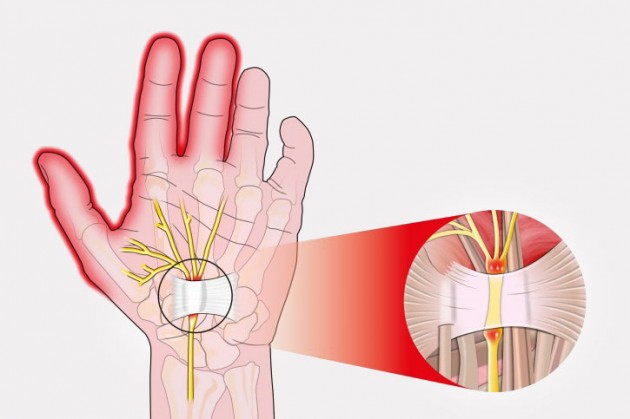

CTSyndrome – System cieśni nadgarstka

Zespół cieśni nadgarstka to najczęstsza neuropatia uciskowa spotykana w gabinetach lekarskich. Spowodowana jest uciskiem nerwu, który biegnie wzdłuż kanału nadgarstka. Najczęstszą przyczyną pojawienia się cieśni jest zapalenie pochewki ścięgna zginaczy, reumatoidalne zapalenie stawów, ciąża, amyloidoza oraz bezpośredni ucisk, spowodowany niekorzystną pozycją nadgarstka. Zespół cieśni nadgarstka objawia się bólem, drętwieniem, osłabieniem ręki i parestezją, promieniującą do kciuka, palca wskazującego, środkowego i serdecznego.  Najlepszym sposobem na zwalczanie zespołu cieśni nadgarstka jest stosowanie ortezy, wyposażonej w stalkę anatomiczną. Natomiast, wielu pacjentów nie zdaje sobie sprawy, że stosując tradycyjną ortezę nadgarstka, pogarszają swój stan! Bezpośredni ucisk, który dostarcza stalka, powoduje pogłębienie problemu i zwiększenie dolegliwości bólowych. Co więcej pacjent, który nigdy nie miał zespołu cieśni nadgarstka, stosujący zwykłą ortezę z powodu np. złamania w obrębie nadgarstka, po kilkutygodniowym okresie unieruchomienia stawu i ciągłej kompresji troczka, w większości przypadków zacznie cierpieć z powodu cieśni. Dlatego, niezmiernie ważne jest stosowanie ortez nadgarstka z odciążeniem kanału nadgarstka. REH4MAT, jako lider w dziedzinie zaopatrzenia ortopedycznego, wprowadził do większości swoich ortez rozwiązanie o nazwie CTSyndrome. Jest to specjalna pelota, umieszczona na stalce i zabezpieczająca kanał nadgarstka przed bezpośrednim uciskiem oraz zapewniająca swobodny przepływ impulsów elektrycznych w nerwie pośrodkowym.

Najlepszym sposobem na zwalczanie zespołu cieśni nadgarstka jest stosowanie ortezy, wyposażonej w stalkę anatomiczną. Natomiast, wielu pacjentów nie zdaje sobie sprawy, że stosując tradycyjną ortezę nadgarstka, pogarszają swój stan! Bezpośredni ucisk, który dostarcza stalka, powoduje pogłębienie problemu i zwiększenie dolegliwości bólowych. Co więcej pacjent, który nigdy nie miał zespołu cieśni nadgarstka, stosujący zwykłą ortezę z powodu np. złamania w obrębie nadgarstka, po kilkutygodniowym okresie unieruchomienia stawu i ciągłej kompresji troczka, w większości przypadków zacznie cierpieć z powodu cieśni. Dlatego, niezmiernie ważne jest stosowanie ortez nadgarstka z odciążeniem kanału nadgarstka. REH4MAT, jako lider w dziedzinie zaopatrzenia ortopedycznego, wprowadził do większości swoich ortez rozwiązanie o nazwie CTSyndrome. Jest to specjalna pelota, umieszczona na stalce i zabezpieczająca kanał nadgarstka przed bezpośrednim uciskiem oraz zapewniająca swobodny przepływ impulsów elektrycznych w nerwie pośrodkowym.

Najlepszym sposobem na zwalczanie zespołu cieśni nadgarstka jest stosowanie ortezy, wyposażonej w stalkę anatomiczną. Natomiast, wielu pacjentów nie zdaje sobie sprawy, że stosując tradycyjną ortezę nadgarstka, pogarszają swój stan! Bezpośredni ucisk, który dostarcza stalka, powoduje pogłębienie problemu i zwiększenie dolegliwości bólowych. Co więcej pacjent, który nigdy nie miał zespołu cieśni nadgarstka, stosujący zwykłą ortezę z powodu np. złamania w obrębie nadgarstka, po kilkutygodniowym okresie unieruchomienia stawu i ciągłej kompresji troczka, w większości przypadków zacznie cierpieć z powodu cieśni. Dlatego, niezmiernie ważne jest stosowanie ortez nadgarstka z odciążeniem kanału nadgarstka. REH4MAT, jako lider w dziedzinie zaopatrzenia ortopedycznego, wprowadził do większości swoich ortez rozwiązanie o nazwie CTSyndrome. Jest to specjalna pelota, umieszczona na stalce i zabezpieczająca kanał nadgarstka przed bezpośrednim uciskiem oraz zapewniająca swobodny przepływ impulsów elektrycznych w nerwie pośrodkowym.

Najlepszym sposobem na zwalczanie zespołu cieśni nadgarstka jest stosowanie ortezy, wyposażonej w stalkę anatomiczną. Natomiast, wielu pacjentów nie zdaje sobie sprawy, że stosując tradycyjną ortezę nadgarstka, pogarszają swój stan! Bezpośredni ucisk, który dostarcza stalka, powoduje pogłębienie problemu i zwiększenie dolegliwości bólowych. Co więcej pacjent, który nigdy nie miał zespołu cieśni nadgarstka, stosujący zwykłą ortezę z powodu np. złamania w obrębie nadgarstka, po kilkutygodniowym okresie unieruchomienia stawu i ciągłej kompresji troczka, w większości przypadków zacznie cierpieć z powodu cieśni. Dlatego, niezmiernie ważne jest stosowanie ortez nadgarstka z odciążeniem kanału nadgarstka. REH4MAT, jako lider w dziedzinie zaopatrzenia ortopedycznego, wprowadził do większości swoich ortez rozwiązanie o nazwie CTSyndrome. Jest to specjalna pelota, umieszczona na stalce i zabezpieczająca kanał nadgarstka przed bezpośrednim uciskiem oraz zapewniająca swobodny przepływ impulsów elektrycznych w nerwie pośrodkowym.To jest wyrób medyczny.